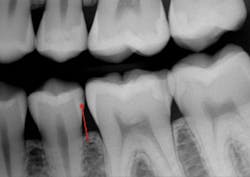

Your observations are shared by the majority of mature practitioners. Many younger practitioners have not noticed the inadequacy of periapical and bitewing radiographs because they do not have a historical perspective relative to the problem you described. I recently received a typical example from an excellent general practitioner in the eastern part of the US (figures 1 and 2).

Upon initial examination of the radiograph, only a few minor lesions were observed. When the dentist excavated the caries in the maxillary second molar, the extreme depth of the lesion was able to be seen. This is not an abnormal finding. In spite of the ability to manipulate digital images through magnification, coloring, texturing, and change of contrast, most small lesions and some large lesions are often missed.

Figure 1: Note the lack of any clearly identifiable presence of deep carious lesions on this current-generation digital radiograph.